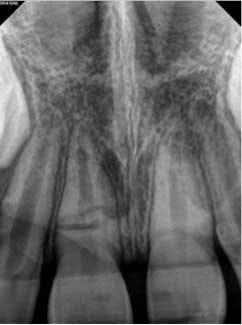

A 7-year-old male presented to my office following an accident that resulted in a horizontal root fracture of tooth No. 8. Upon examination, the general dentist had splinted the central incisors together using a rigid splint. Clinical testing on tooth No. 8 revealed that this tooth had a nonlingering response to cold and displayed slight tenderness to palpation. All other testing on teeth Nos. 7 and 9 was within normal limits (WNL). Radiographically, the apices of both central incisors were incompletely developed and a horizontal root fracture was noted at the junction of the coronal and middle third of the root on tooth No. 8 (figure 1). Due to the positive response to cold and lack of symptoms to percussion, bite, and palpation, I recommended retesting in three weeks and removal of the splint.